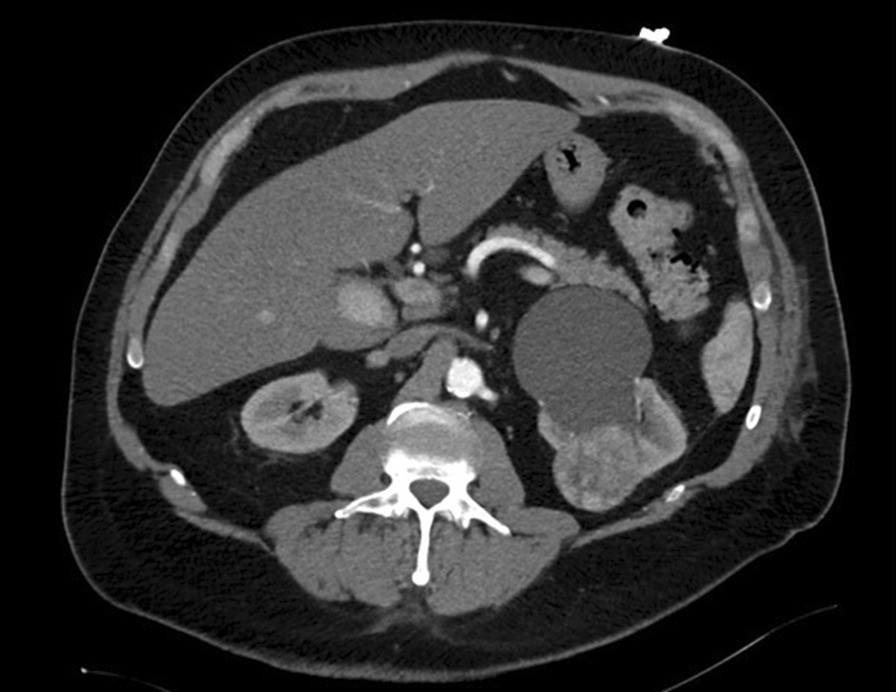

Fig. 2From: Acute myocardial infarction and arterial embolism in a patient with newly diagnosed renal mass: management dilemmas! A case reportAbdominal CT scan showing a renal tumor of the left side with adjacent renal cystBack to article page